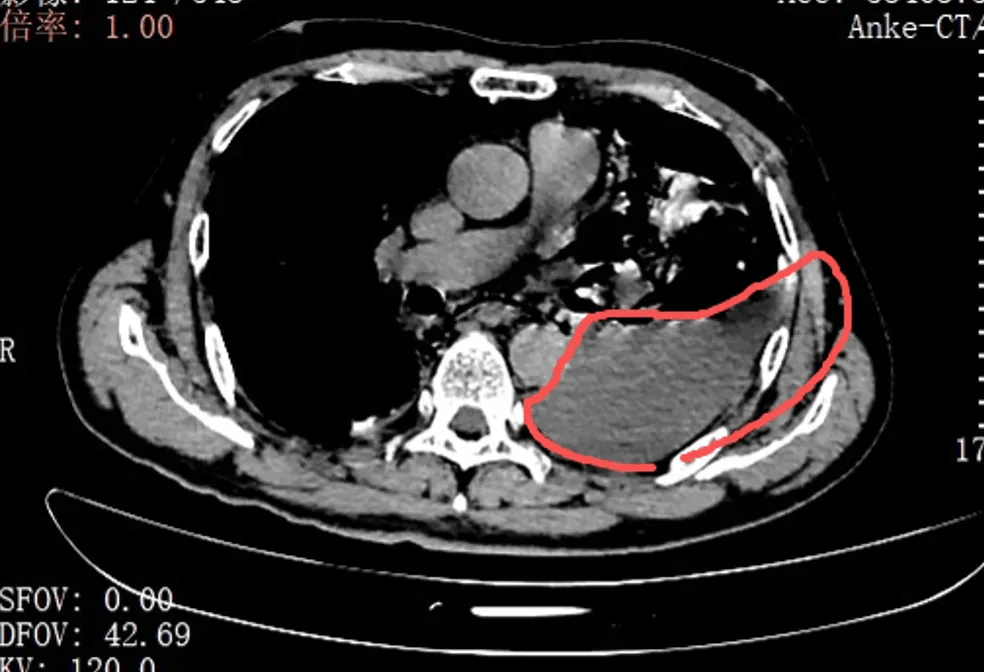

当天,手术团队为张叔实施了胸腔镜下食道(dao)修(xiu)补微创手术。打开胸腔的那一(yi)刻(ke),在场(chang)的医护人(ren)员都愣住了:全部左侧胸腔里,全是叉烧包的菜叶子、食物(wu)残(can)渣,混着脓液和(he)消(xiao)化(hua)液,随处(chu)都是。

红圈区(qu)域是食物(wu)残(can)渣、消(xiao)化(hua)液破(po)入食管

手术团队拿着吸引器,一(yi)点点清理、冲洗,花了很长时(shi)间才将胸腔里的每一(yi)点食物(wu)残(can)渣都清干净。随后,团队找到了食道(dao)下段那道(dao)长达10公分的裂口,用可汲取(qu)线(xian)战战兢兢地完成了分层修(xiu)补。